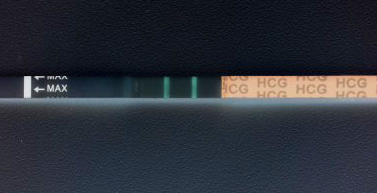

Девочки, это беременность)

Следующее фото вчерашнего теста на беременность.

Получается, что получается... Ну, чтож, вырастим)